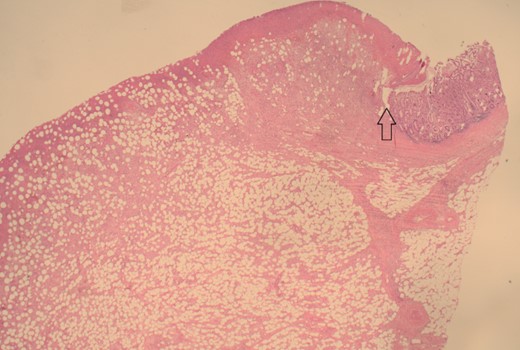

The patient was taken to the theatre for an emergency laparotomy. Intraoperative findings were of high-grade SBO, secondary to terminal ileal intussusception. The involved small bowel was viable with no perforation. The intussusception was reduced. Nidus was an intraluminal polypoid lesion. A small bowel resection and a primary, double-layered hand-sewn anastomosis were performed. A specimen was sent for histology. Histology confirmed an ulcerated benign submucosal lipoma (45 × 30 × 22 mm) as the cause (Figs 4–7).

12.5× magnification showing the intact surface small bowel mucosa with the underlying lipoma.

12.5× magnification showing the junction between the ulcerated leading point of the intussusception on the left and the preserved mucosa on the right of the arrow.

100× magnification showing the ulcerated surface of the lipoma which is covered by fibrin and neutrophils. The clear cystic spaces below this are the residual fat cells.

100× magnification of the lipoma illustrating the adipocytes which show cytoplasmic distention by optically clear fat.